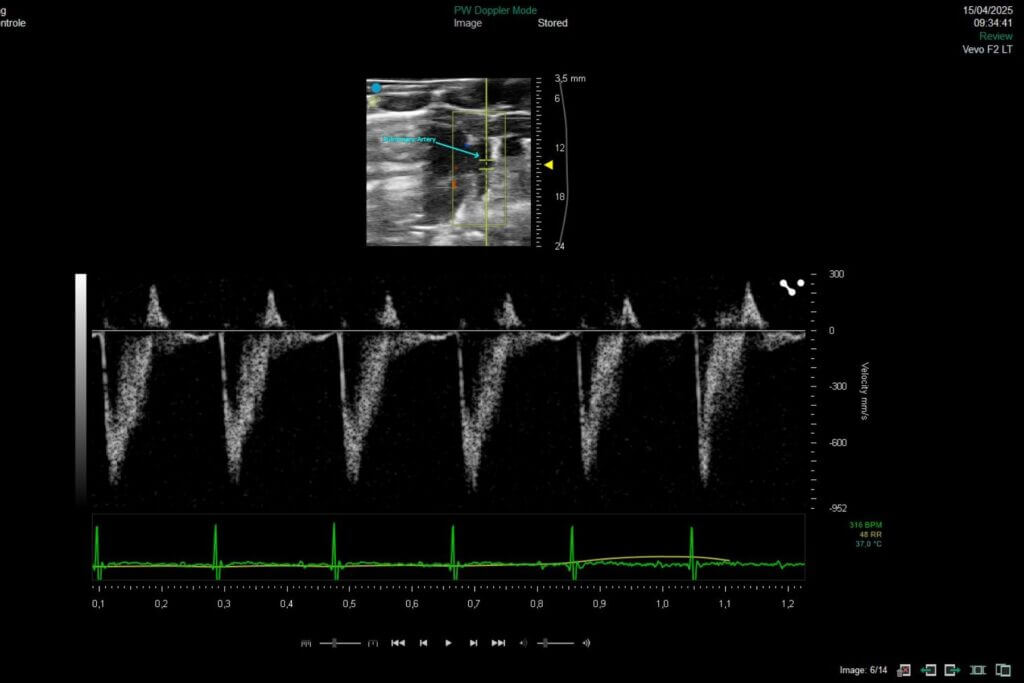

Our platform enables the direct evaluation of therapeutic candidates in both HFrEF and HFpEF models, integrating comprehensive assessments of left ventricular function by echocardiography, cardiac remodeling, and cardio-renal-metabolic interactions.

Permanent coronary artery ligation model

The permanent left coronary artery ligation model is based on the definitive ligation of this artery, inducing a large myocardial infarction and progressive left‑ventricular failure. It recapitulates key mechanisms of post‑infarction remodeling: necrosis, inflammation, fibrosis, and long‑lasting impairment of cardiac function. This model is a robust tool for evaluating cardioprotective, antifibrotic, or regenerative therapies.

Ischemia-reperfusion injury model (IRI)

The myocardial ischemia–reperfusion (IRI) model consists in transient occlusion of the left coronary artery to reproduce the damage caused by tissue reperfusion following a treated myocardial infarction. This approach generates massive oxidative stress, acute inflammation, significant apoptosis, and early myocardial remodeling. This model provides an ideal platform for evaluating cardioprotective, antioxidant, or anti‑inflammatory therapies targeting reperfusion‑induced injury.

Dahl rat model

The salt‑sensitive Dahl rat model progressively and physiologically reproduces the mechanisms of HFpEF. When exposed to a high‑salt diet, these animals develop severe hypertension, concentric left‑ventricular remodeling, myocardial fibrosis, and impaired cardiac relaxation, while maintaining a preserved ejection fraction.